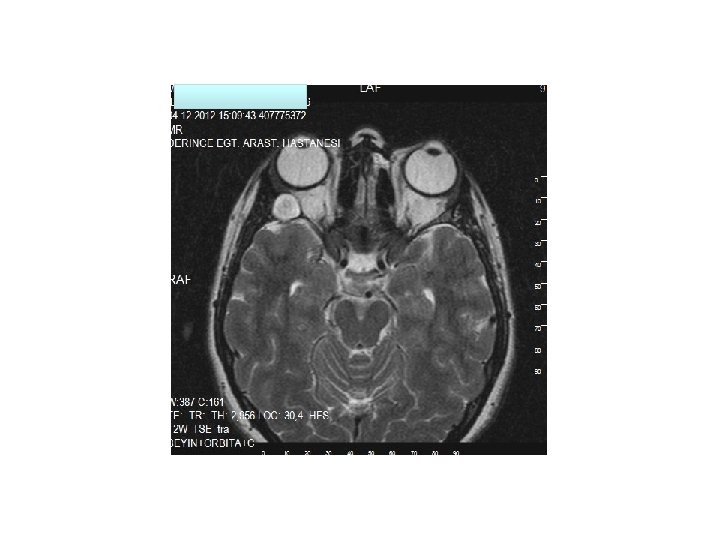

• Sağ orbita lateral duvarda yumuşak doku komponenti olan litik lezyon. Lezyon sol lateral rektus kası ve lakrimal glanda hafif itmektedir.

Kranial MR: • Sağ orbita lateral duvarı komşuluğunda 13 mm çapında kistik natürde kitle lezyonu izlenmektedir. • Sol ethmoid sol frontal sinüste mukozal kalınlaşma izlenmektedir.